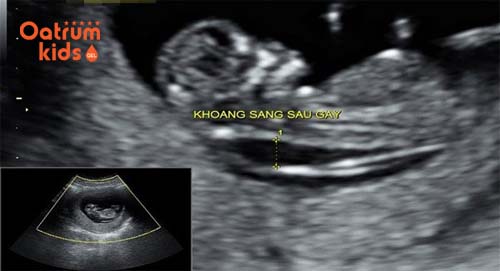

Khi tiến hành đo khoảng sáng sau gáy bác sĩ sẽ đo chiều dài tính từ đỉnh đầu của thai nhi đến cuối xương sống thai nhi, tiếp tục đo độ mờ da gáy. Đây chính là đường trắng ở sau gáy của thai nhi trong khi vùng xung quanh có màu tối sẫm hơn. Đó cũng là lý do vì sao người ta gọi là khoảng sáng sau gáy.